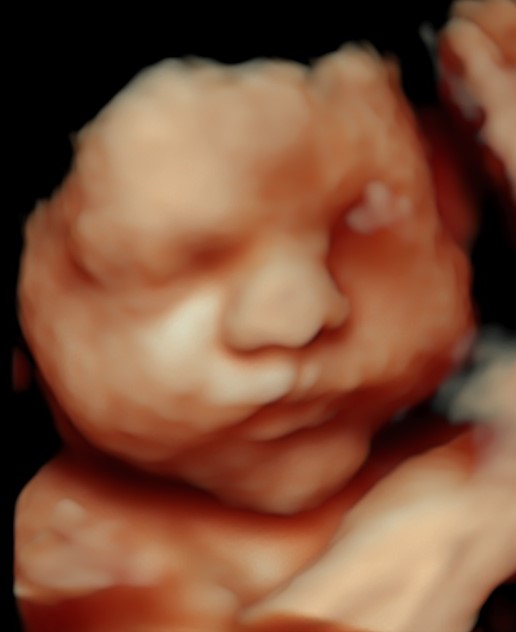

4D/5D/HD Ultrasound Gallery

Gallery